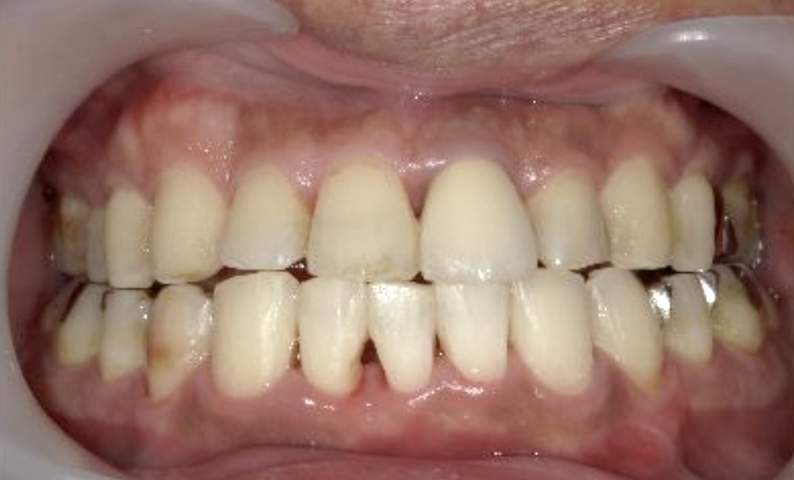

症例_002 上顎だけの部分矯正

治療期間:7ヶ月金額:30万円+税女性前歯のガタガタ上の前歯だけ

| Before | After |

|---|---|

|